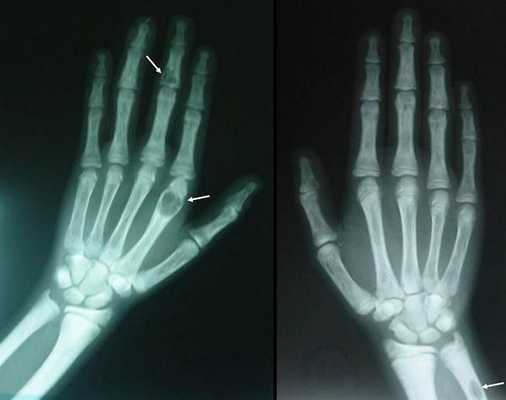

Для оценки тяжести поражения костной системы проводится рентгенография костей стоп, кистей, голени, черепа, денситометрия. Типично выявление признаков диффузной деминерализации костной ткани или фиброзно-кистозного остита. При обзорной урографии, УЗИ почек и мочевого пузыря обнаруживаются одиночные или множественные камни. Состояние органов пищеварения оценивается с помощью УЗИ брюшной полости (желчного пузыря, поджелудочной железы), ЭГДС. При сердечно-сосудистой симптоматике показано выполнение ЭКГ, ЭхоКГ, суточного мониторирования ЭКГ и АД.

На поздней стадии костного гиперпаратиреоза происходит размягчение, искривления, патологические переломы (при обычных движениях, в постели) костей, возникают рассеянные боли в костях рук и ног, позвоночнике. В результате остеопороза челюстей расшатываются и выпадают здоровые зубы. Из-за деформации скелета больной может стать ниже ростом. Патологические переломы малоболезненны, но заживают очень медленно, часто с деформациями конечностей и образованием ложных суставов. На руках и ногах обнаруживаются периартикулярные кальцинаты. На шее в области паращитовидных желез можно пальпировать большую аденому.

У большинства пациентов при аденоме паращитовидной железы развивается костная форма гиперпаратиреоза. Поражение костной системы проявляется генерализованным фиброзно-кистозным оститом, остеопорозом, патологическими переломами трубчатых костей и тел позвонков, расшатыванием и выпадением зубов. Почечная форма гиперпаратиреоза, ассоциированного с аденомой паращитовидной железы, может протекать в виде мочекаменной болезни или диффузного нефрокальциноза.

Длительное течение заболевания сказывается на формировании костей. Так, н а поздних стадиях вовремя не диагностированного гиперпаратиреоза наблюдаются:

- разрушение дистальных или концевых фаланг конечностей;